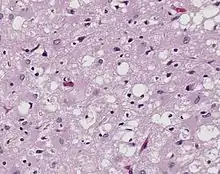

التعامل مع الحيوانات المريضة عامل خطر على العمال الزراعيين. والأمراض حيوانية المنشأ هي الأمراض التي تنتقل من الحيوانات المصابة إلى البشر. وتنجم معظم الأمراض حيوانية المنشأ عن الكائنات الحية، مثل الطفيليات، والبكتيريا، والبريونات، والفطريات، والأوليات، والفيروسات التي تعيش داخل الحيوان ولكنها يمكن أن تكون مسببة للأمراض عند البشر. ويمكن أن يؤدي الانتقال المباشر أو غير المباشر من البراز أو السوائل الجسدية إلى الإصابة، كما يمكن أن يؤدي استهلاك المنتجات الحيوانية الملوثة إلى الإصابة بالعدوى.[21] وبسبب اتصالهم الوثيق بالحيوانات، أصبح المزارعون والأطباء البيطريون والمربيون وغيرهم من العمال الزراعيين أكثر عرضة للإصابة بالأمراض حيوانية المنشأ.